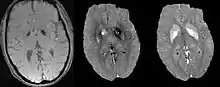

Morphology Enabled Dipole Inversion (MEDI)[13]

A unique advantage of MRI is that it provides not only the phase image but also the magnitude image. In principle, the contrast change, or equivalently the edge, on a magnitude image arises from the underlying change of tissue type, which is the same cause for the change of susceptibility. This observation is translated into mathematics in MEDI, where edges in a QSM which do not exist in the corresponding magnitude image are sparsified by solving a weighted norm minimization problem.[14]

MEDI has also been validated extensively in phantom, in vitro and ex vivo experiments. In in vivo human brain, MEDI calculated QSM showed similar results compared to COSMOS without statistically significant difference.[15] MEDI only requires a single angle acquisition, so it is a more practical solution to QSM.